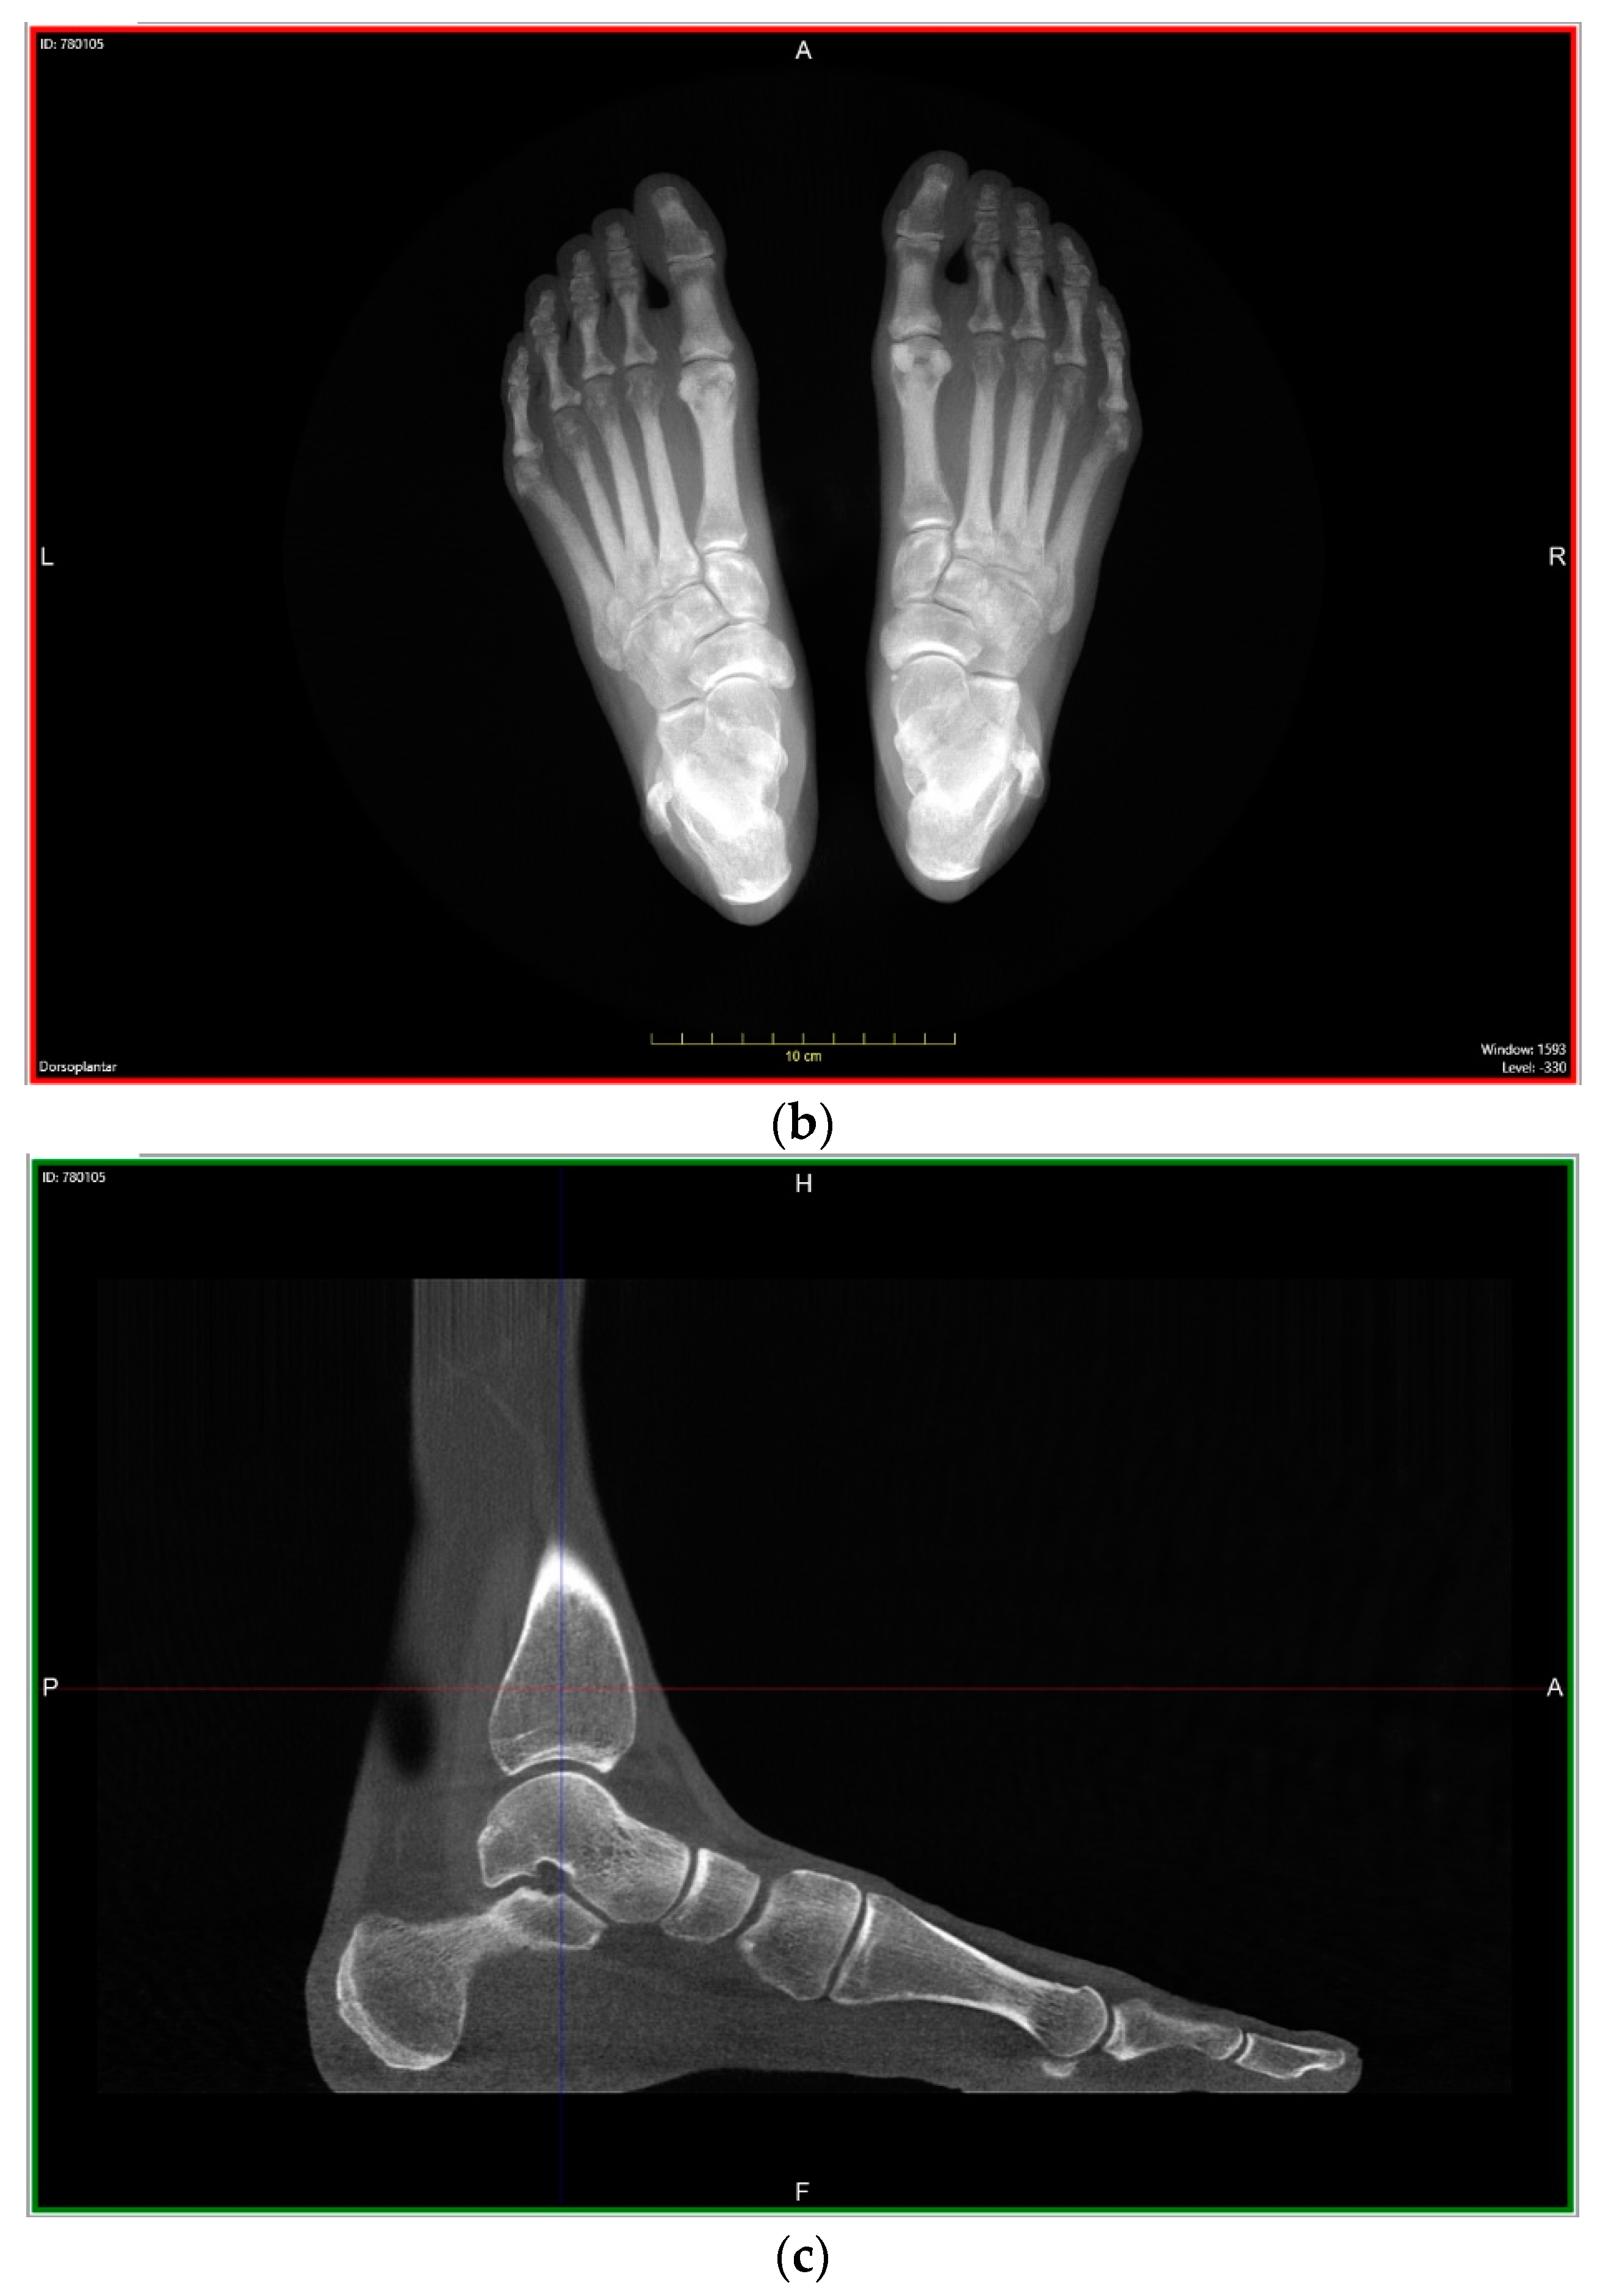

Recent Innovations Brought about by Weight-Bearing CT Imaging in the Foot and Ankle: A Systematic Review of the Literature

:1. Introduction

4.2.1. Description of Techniques for Image Acquisition